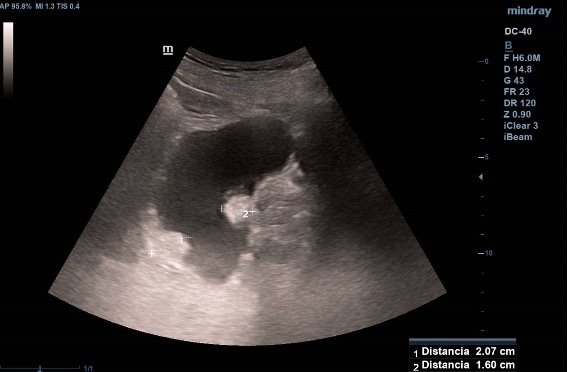

Ecografía vesical: Pared irregular, múltiples lesiones polipoides, la mayor (2.07 cm) en pared posteroinferior. Una lesión polipoiea dependiente de la próstata de 1,6 cm. Otra lesión más craneal en pared posterior de 1.26 cm, y cerca de uréter derecho una de 2 cm.  Además, varias lesiones polipoides más pequeñas en cara anterior y lateral derecha.